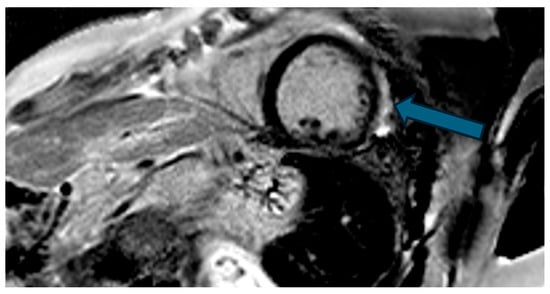

| 1 | Female, 61 years old | Syncope | 11 | MVP, mitral regurgitation | Lateral | Holter: atrial tachycardia and ventricular ectopy; cardiology follow-up planned for possible mitral valve repair |

| 2 | Male, 52 years old | Syncope and atypical chest pain | 10 | - | Lateral | History of ventricular arrhythmias; cardiology follow-up and Holter monitoring recommended |

| 3 | Female, 74 years old | Extrasystole | 3 | - | No LGE | No LGE; patient reassured and scheduled for periodic clinical follow-up |

| 4 | Male, 34 years old | Extrasystole in Marfan syndrome | 15 | MVP, valvular regurgitation | No LGE | Marfan syndrome; MVP with regurgitation; regular cardiology follow-up advised. |

| 5 | Male, 63 years old | Heart failure | 2,5 | MVP, valvular regurgitation | No LGE | Reduced LVEF (47%) with left atrial dilatation; heart failure therapy optimized; follow-up planned. |

| 6 | Male, 68 years old | Palpitations | 5 | - | Lateral | LGE in basal lateral wall; electrophysiological evaluation and ECG monitoring recommended. |

| 7 | Female, 53 years old | Extrasystole and syncope | 15 | MVP, valvular regurgitation | Basal-lateral | Extensive MAD with MVP and LGE; increased arrhythmic risk; antiarrhythmic therapy considered. |

| 8 | Female, 63 years old | Aortic and mitral regurgitation | 11 | Aortic and mitral regurgitation | Lateral | Aorto-mitral regurgitation with septal hypokinesia; mitral valve repair performed; heart failure therapy started. |

| 9 | Male, 45 years old | Palpitations and vertigo | 10 | - | Lateral | Basal lateral LGE; regular clinical and ECG follow-up recommended |